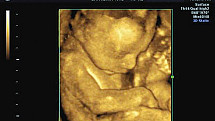

Czy embriony mogą same się leczyć?

Niedziela, 8 maja 2016

O pułapkach diagnostyki prenatalnej pisze prof. Bogdan Chazan